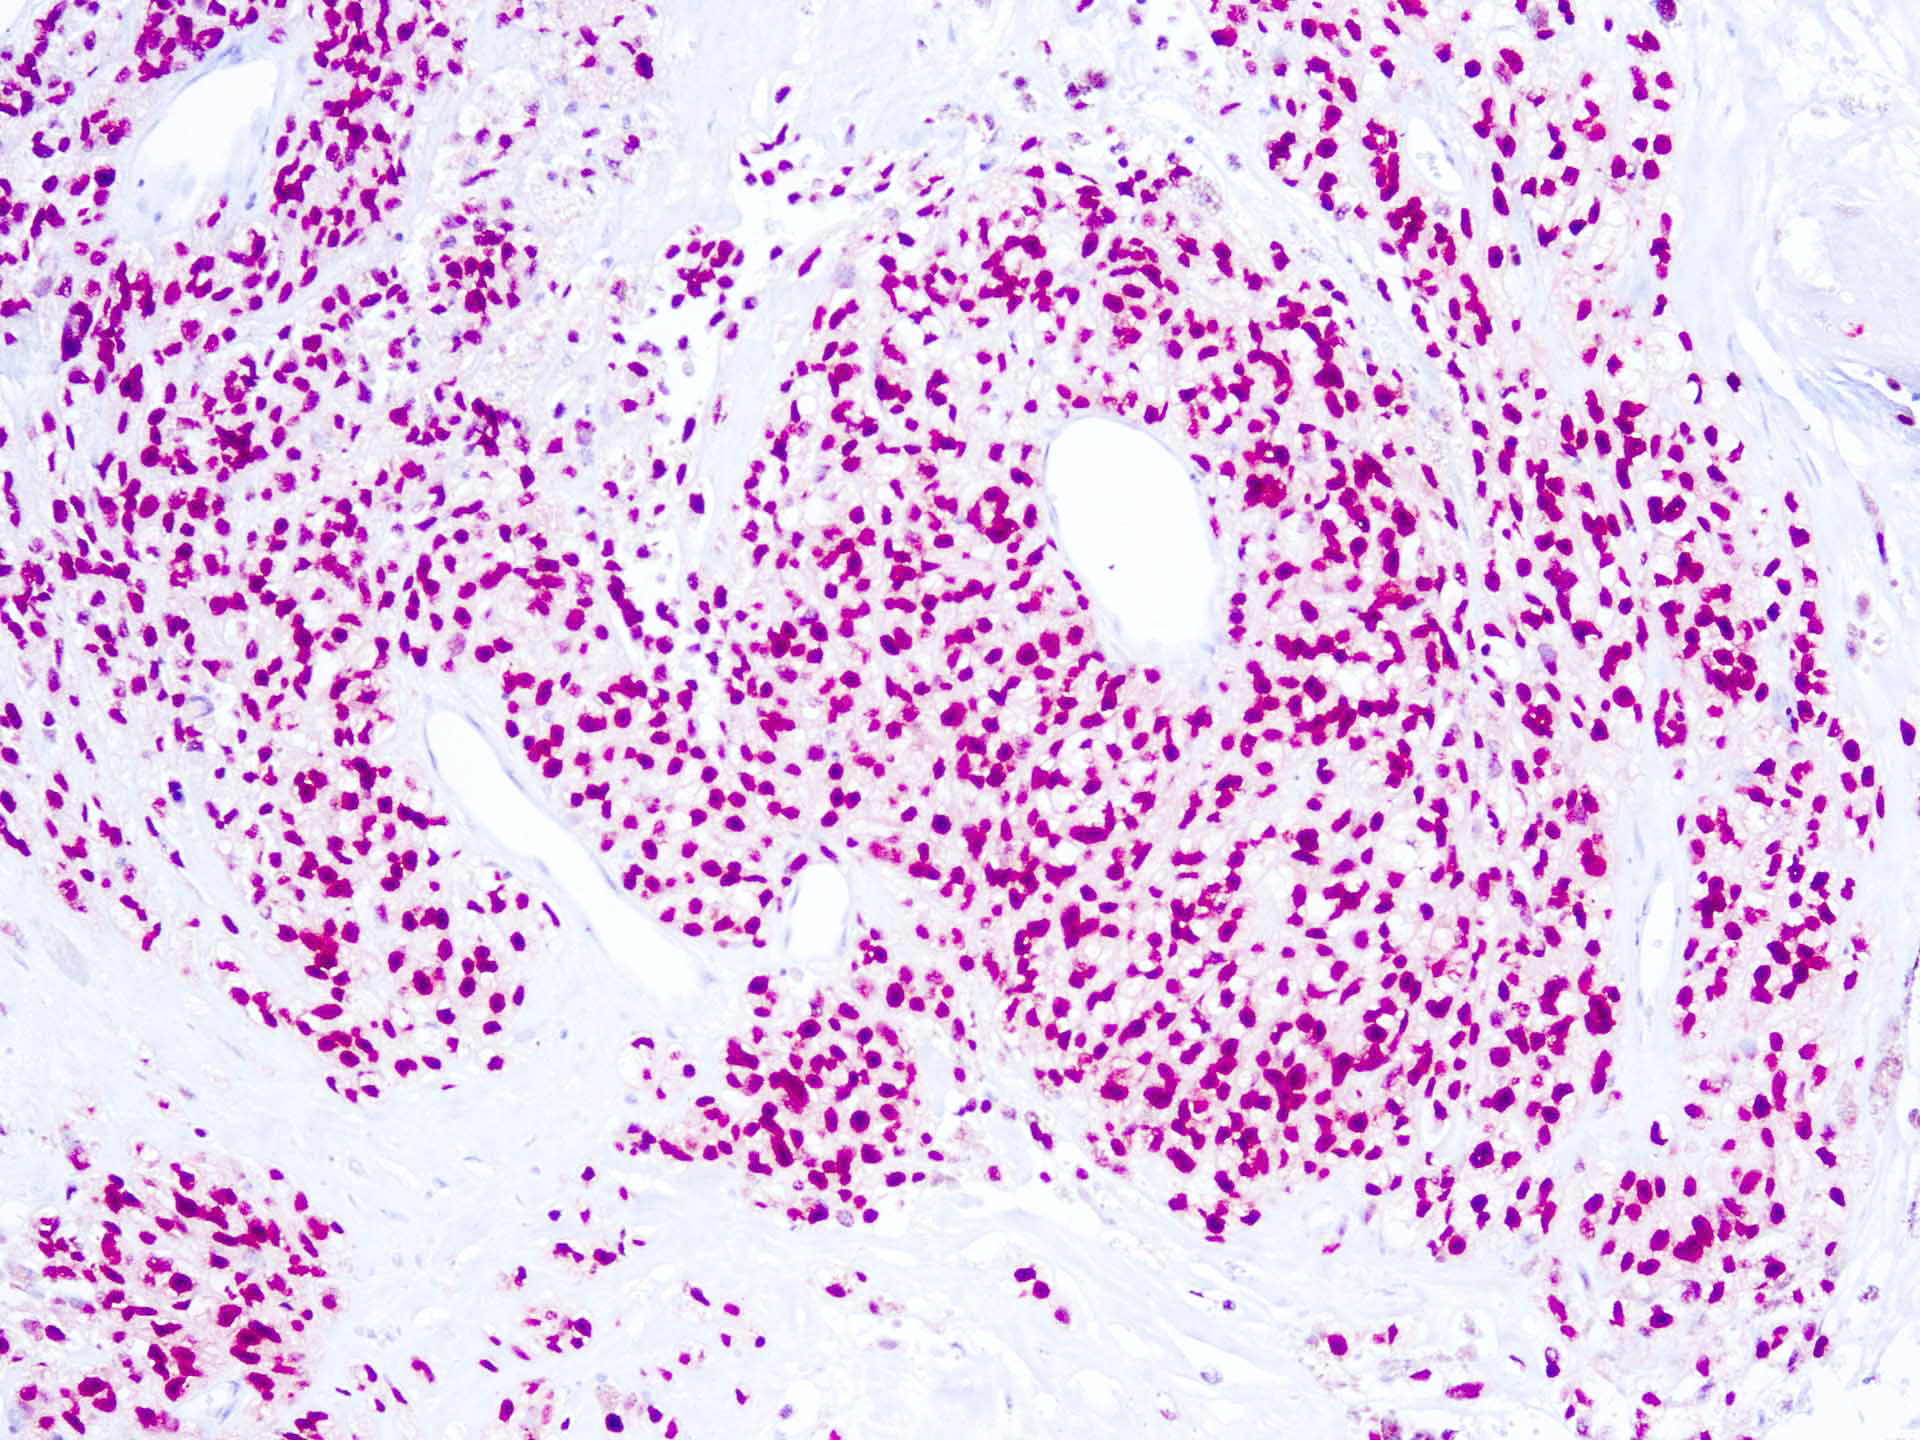

SOX-10, a member of the sex-determining region Y-related HMG-box family, is a transcription factor that is expressed in pre-migratory and migrating neural crest cells. Following migration it remains expressed in cells destined for glial, schwannian, and melanocytic differentiation. SOX10 is widely expressed in normal human tissues including melanocytes and breast tissue. SOX10 is also an important marker in malignant tumors such as melanoma, and breast carcinomas of basal-like and triple negative type, gliomas, and benign tumors such as schwannomas. More importantly, SOX10 has been shown to be expressed in 97-100% of desmoplastic and spindle cell melanomas and has also been shown to be expressed in 100% of nevi. Spindle cell and desmoplastic melanomas are rare variants of invasive cutaneous melanoma, with an annual incidence rate of approximately 2 per 100,000. The majority of oligodendrogliomas and a large percentage of astrocytomas and poorly differentiated glioblastomas have also been shown to express SOX10.

| Positive Control Tissue | Melanoma |